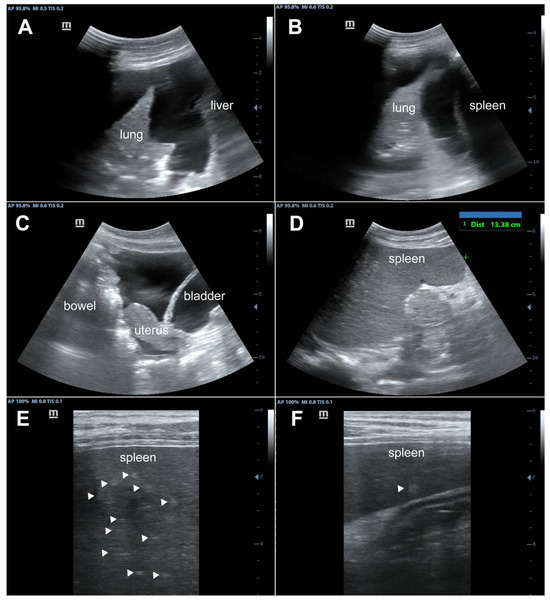

| Day 2 | Ultrasound revealed bilateral pleural effusions, pelvic free fluid, and hyperechoic splenic lesions consistent with disseminated KS. Right thoracentesis removed 1300 mL blood-stained fluid. Received first cycle of IV paclitaxel 100 mg/m2, IV dexamethasone 12 mg, third dose of ceftriaxone 2 g. |

- Huson, M.A.M.; Kumwenda, T.; Gumulira, J.; Rambiki, E.; Wallrauch, C.; Heller, T. Ultrasound findings in Kaposi sarcoma patients: Overlapping sonographic features with disseminated tuberculosis. Ultrasound J. 2023, 15, 27. [Google Scholar] [CrossRef] [PubMed]

| Day 39 | Clinic visit for paclitaxel cycle 3 with repeat laboratory examinations and ultrasound. Reported adherence to ART regimen. |

| Day 116 | Post treatment follow up visit in clinic with repeat laboratory examinations and ultrasound. Patient felt well and was back in school. |